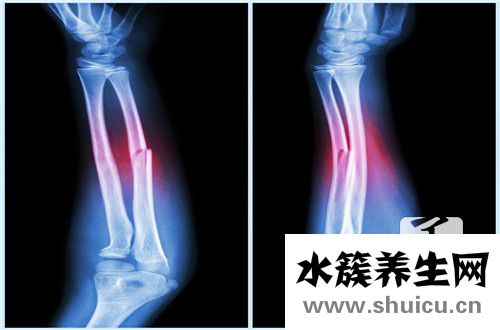

一旦產生骨折,在骨折位置可造成疼痛、發脹、淤點和功能問題,查驗時還可聽見骨斷端互相摩擦的響聲(即骨擦音),另外可能伴隨血管和神經的損害,使身體遠側造成缺血性或覺得發麻、運動障礙的狀況,或造成內臟損傷。骨折后因強烈疼痛,流血過多或高并發頭、胸、腹部內臟器官損害而造成休克。

骨折的確診除病歷和病癥外,須融合X線線片查驗,便于診斷。